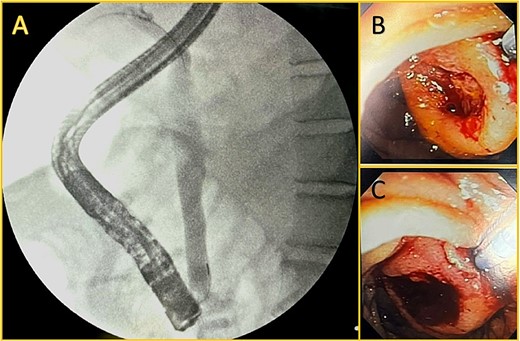

Broad-spectrum antibiotics were initiated (Piperacillin-tazobactam at first and later carbapenem due to the patient's clinical condition and culture results), and the patient responded well; nonetheless, his bilirubin and GGT levels rose over 12 mg/dl and 1234 U/L on his eleventh day in the ICU. Therefore, an endoscopic retrograde cholangiopancreatography (ERCP) was performed. During the procedure, a mass with surface ulceration was identified on the ampulla, which was subsequently biopsied. A 10Fr biliary prosthesis was inserted, freeing the bile duct from that obstruction. (Fig. 2).

Endoscopic retrograde cholangiopancreatography. A: Cholangiography is shown, and successful cannulation of the biliary duct was achieved, with the identification of a dilated duct and no filling defect. B and C: An ampullary mass is shown with surface ulceration.